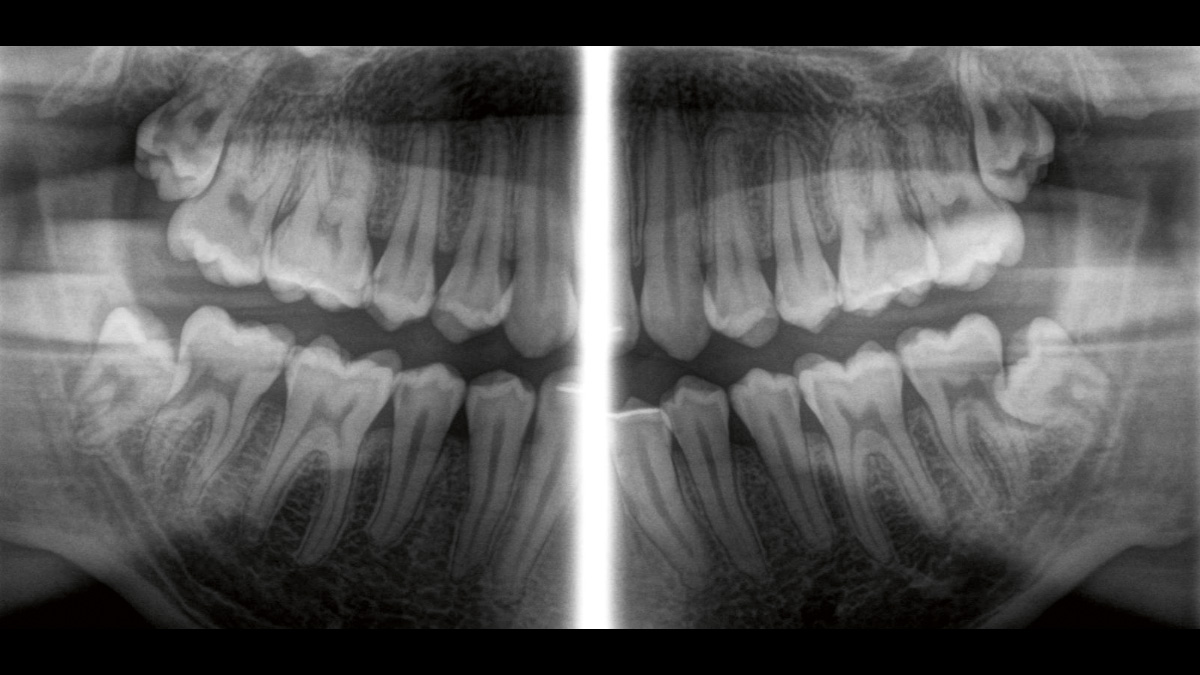

Der Direct Conversion Sensor erfüllt besonders hohe Standards für die 2D-Bildgebung

Der Autofokus erzeugt aus mehreren tausend Einzelbildern automatisch eine beeindruckende scharfe Panorama-Röntgenaufnahme

Der Direct Conversion Sensor (DCS) hat den Standard der Panorama-Bildgebung neu definiert. Röntgenstrahlen werden direkt in elektrische Signale umgewandelt – im Gegensatz zu herkömmlichen Systemen gibt es keinen Signalverlust durch Lichtumwandlung, was eine verbesserte Bildgebung ermöglicht. Das Ergebnis sind Bilder mit einer sehr hohen Schärfe, selbst bei niedriger Dosis.

Eine Röntgenaufnahme muss sofort diagnostizierbar sein. Der Autofokus hilft dabei erheblich. Orthophos SL erfasst mehrere tausend Einzelbilder in einem Zyklus und erkennt automatisch scharfe Bereiche, um ein gleichmäßig scharfes Gesamtbild zu erzeugen. Der intelligente Autofokus erfordert keine manuellen Arbeitsschritte vor und nach der Erfassung.